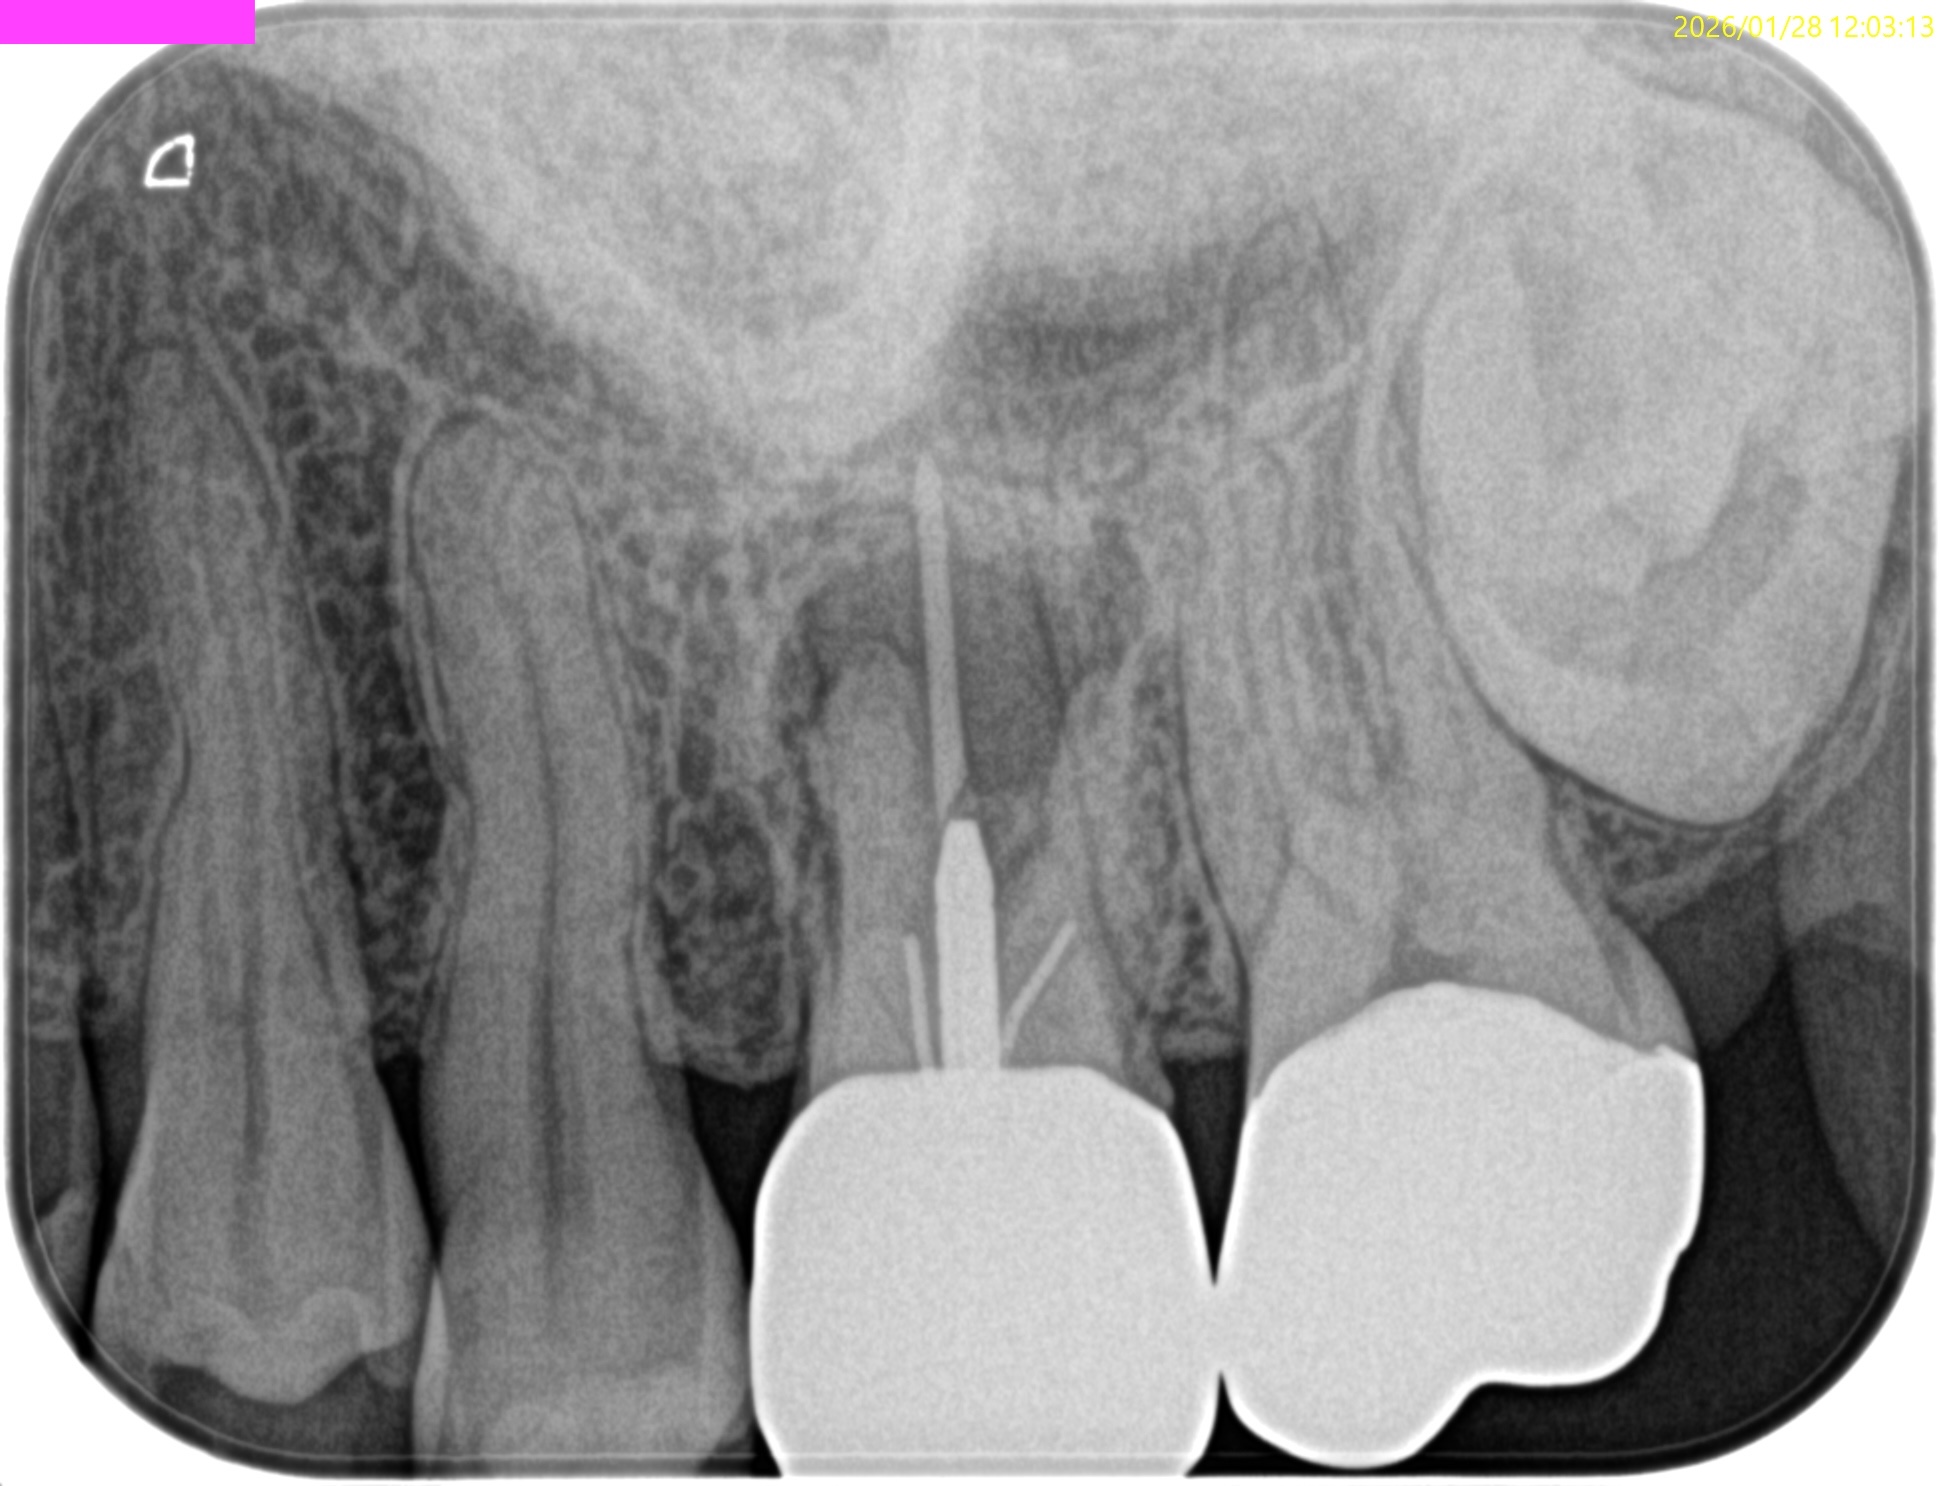

Pre-op Endo Test(2026.1.28)

MB1

MB2

DB

P

Selectiveに再根管治療をするとすれば、

MB1もしくはMB2

MB1とMB2

は穿通させる必要性があるだろう。

が、

Pはその必要があまりないだろう

ということがわかる。

MB2を発見・穿通させる必要があるかどうか?はこのように術前にCBCTを正しく分析すれば予想ができる。

MBは、

MBの作業長の予測は18~19mm(臨床的にはここからクラウンの厚み, この際はMB部分を引く必要性)ということがわかる。

DBは、

DBの作業長予測は17.4mm(ここからDBのクラウンの厚みを引いた長さ)

になろう。

が、正しくはRoot ZXが96%の可能性で正しい位置を提示してくれる。

そのためのガイドマップにCBCTは必須と言える。

術後にPA, CBCTを撮影した。

B

問題はないと思われる。